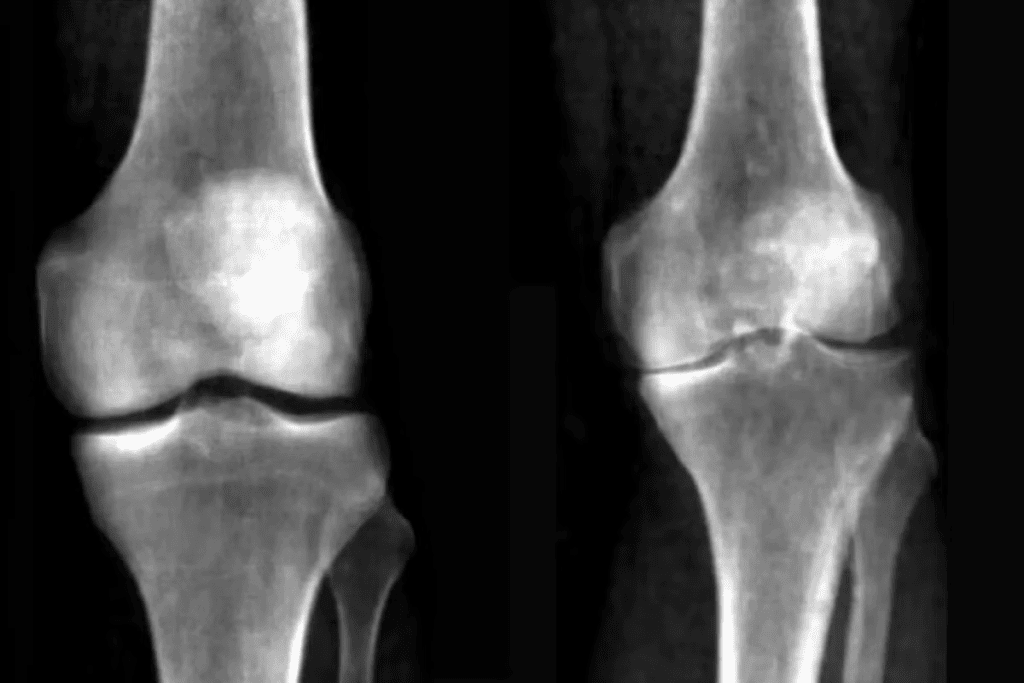

Imaging Tests: X-rays, MRI, and Ultrasound

Imaging tests are key in finding out what’s wrong with your knee. They show us the inside of the knee in detail.

- X-rays: Good for finding bone problems like fractures or arthritis.

- MRI (Magnetic Resonance Imaging): Shows soft tissues like ligaments and cartilage, helping find injuries.

- Ultrasound: Helps check soft tissue injuries and guide treatments.

| Imaging Test | Primary Use | Key Benefits |

| X-rays | Bone fractures, osteoarthritis | Quick, widely available |

| MRI | Soft tissue injuries, meniscal tears | High detail, thorough check |

| Ultrasound | Soft tissue injuries, guided injections | Dynamic check, no radiation |